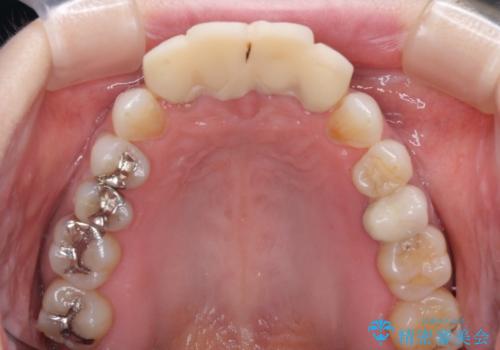

- 自宅近くの歯科医院にて前歯の詰め物が外れたことを機会に、オールセラミッククラウンへの変更を決断して4歯を仮歯に替えたものの、あまりに汚くて恥ずかしいとのことで来院された患者様です。

歯の形成量は不十分で形態は不自然、境目は不適で歯肉が腫れていたため、新しい仮歯に替えた後に歯肉の腫れが引くのを待ち、オールセラミッククラウンにて補綴することとしました。